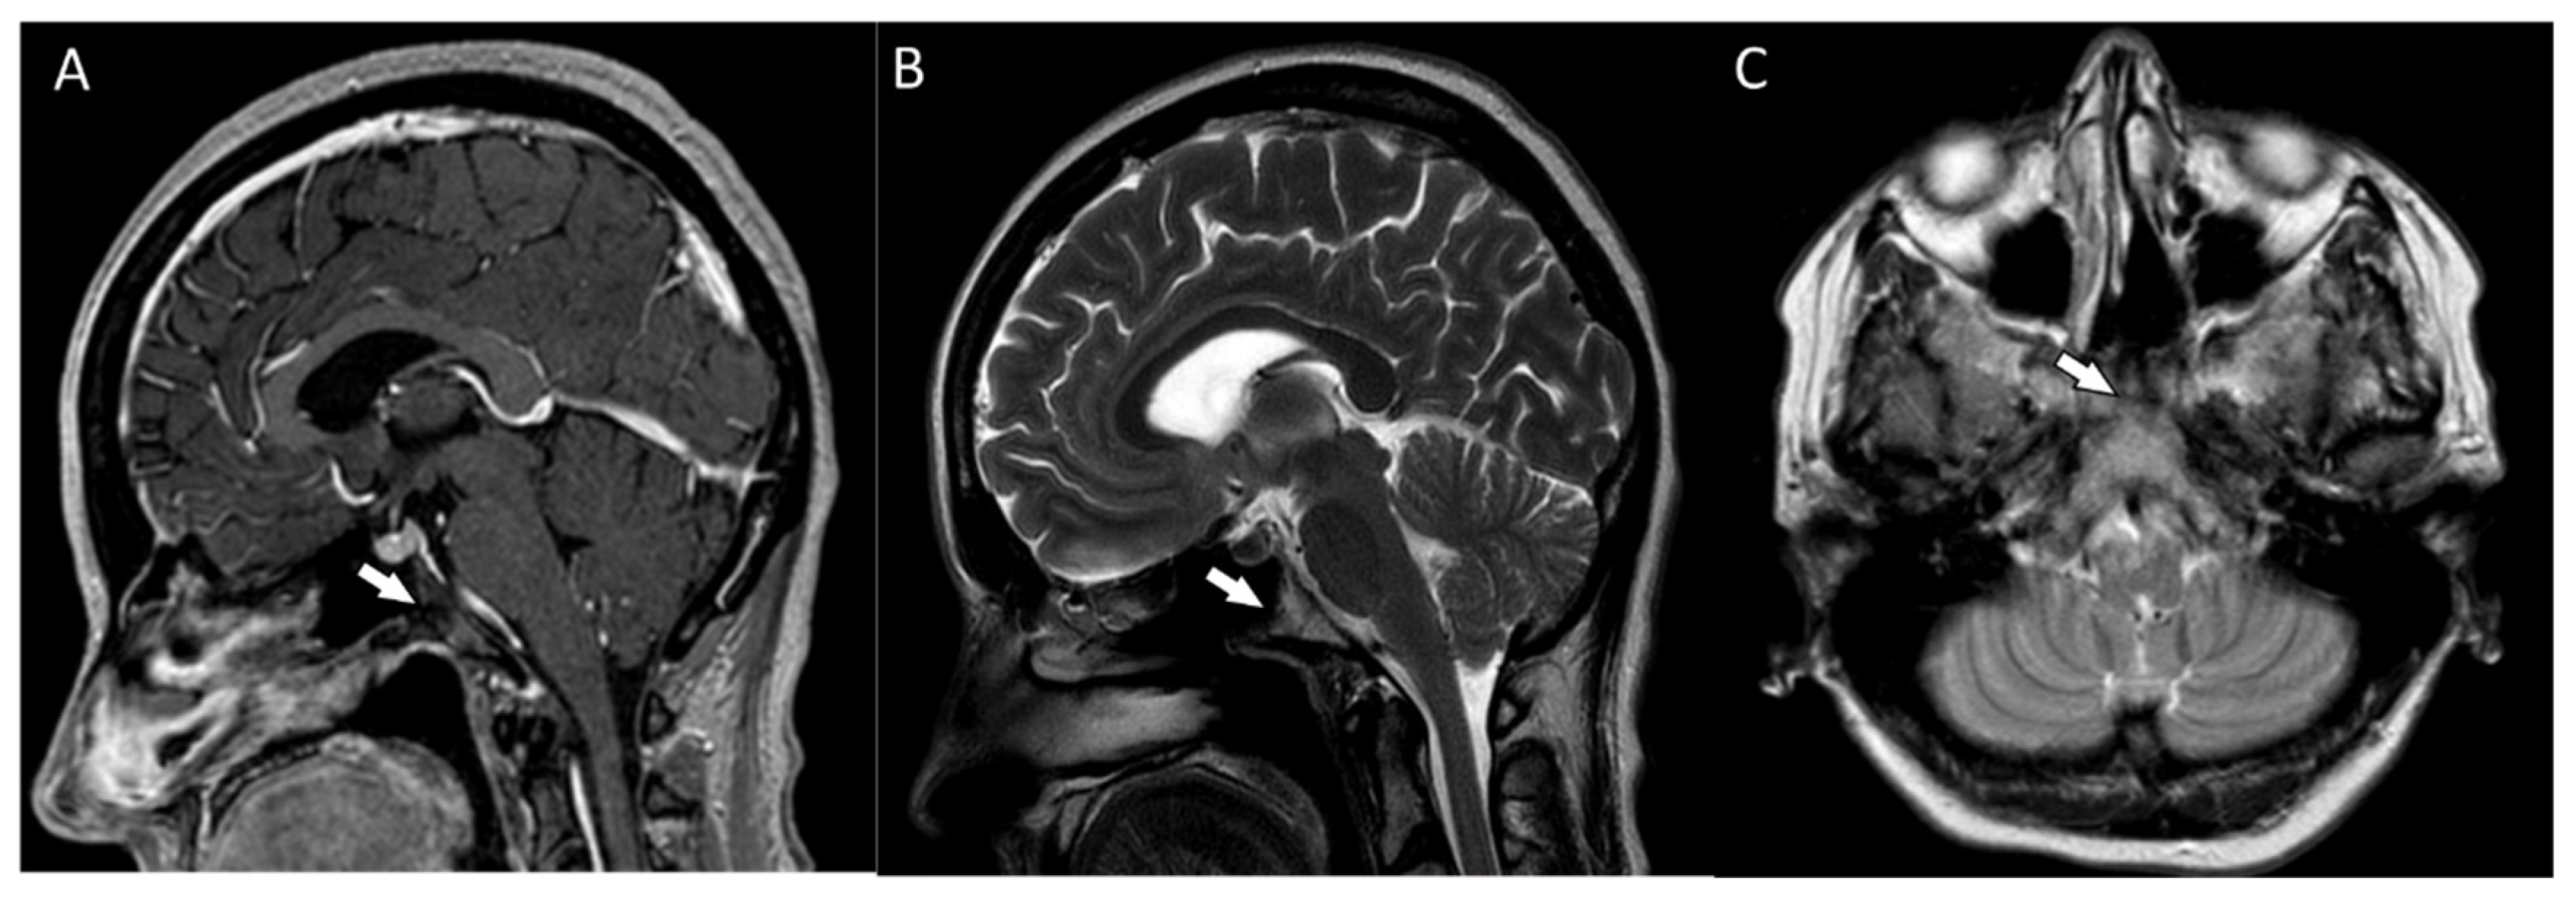

The patient reported nonspecific signs of fatigue and impaired concentration. The magnetic resonance imaging (MRI) of the head revealed a 16 × 18 × 12 mm tumor in the region of the clivus. On T1-weighted imaging, the lesion was isointense and peripherally enhanced after contrast administration. The borders of the lesion were hyperintense while the main part was isointense (Figure 2A). On T2-weighted imaging, the lesion was isointense as well (Figure 2B). On computed tomography (CT), the tumor had smooth outlines with a hypersclerotic rim. It was located centrally and did not show any penetration into the sinuses (Figure 2C). In diffusion-weighted imaging (DWI), no signals of recent ischemic changes were found. The radiology images were also nonspecific and suggested chordoma or fibrous dysplasia.

Figure 2.

(A) The magnetic resonance postcontrast T1-weighted sagittal image, demonstrating the isointense lesion with hyperintense borders (arrow). The image suggested chordoma or fibrous dysplasia (B). The magnetic resonance T2-weighted dark fluid sagittal image, showing the isointense clival lesion (arrow) (C). The computed tomography image, showing the centrally located lesion with a hypersclerotic rim (arrow). The tumor did not infiltrate the sphenoid sinuses.